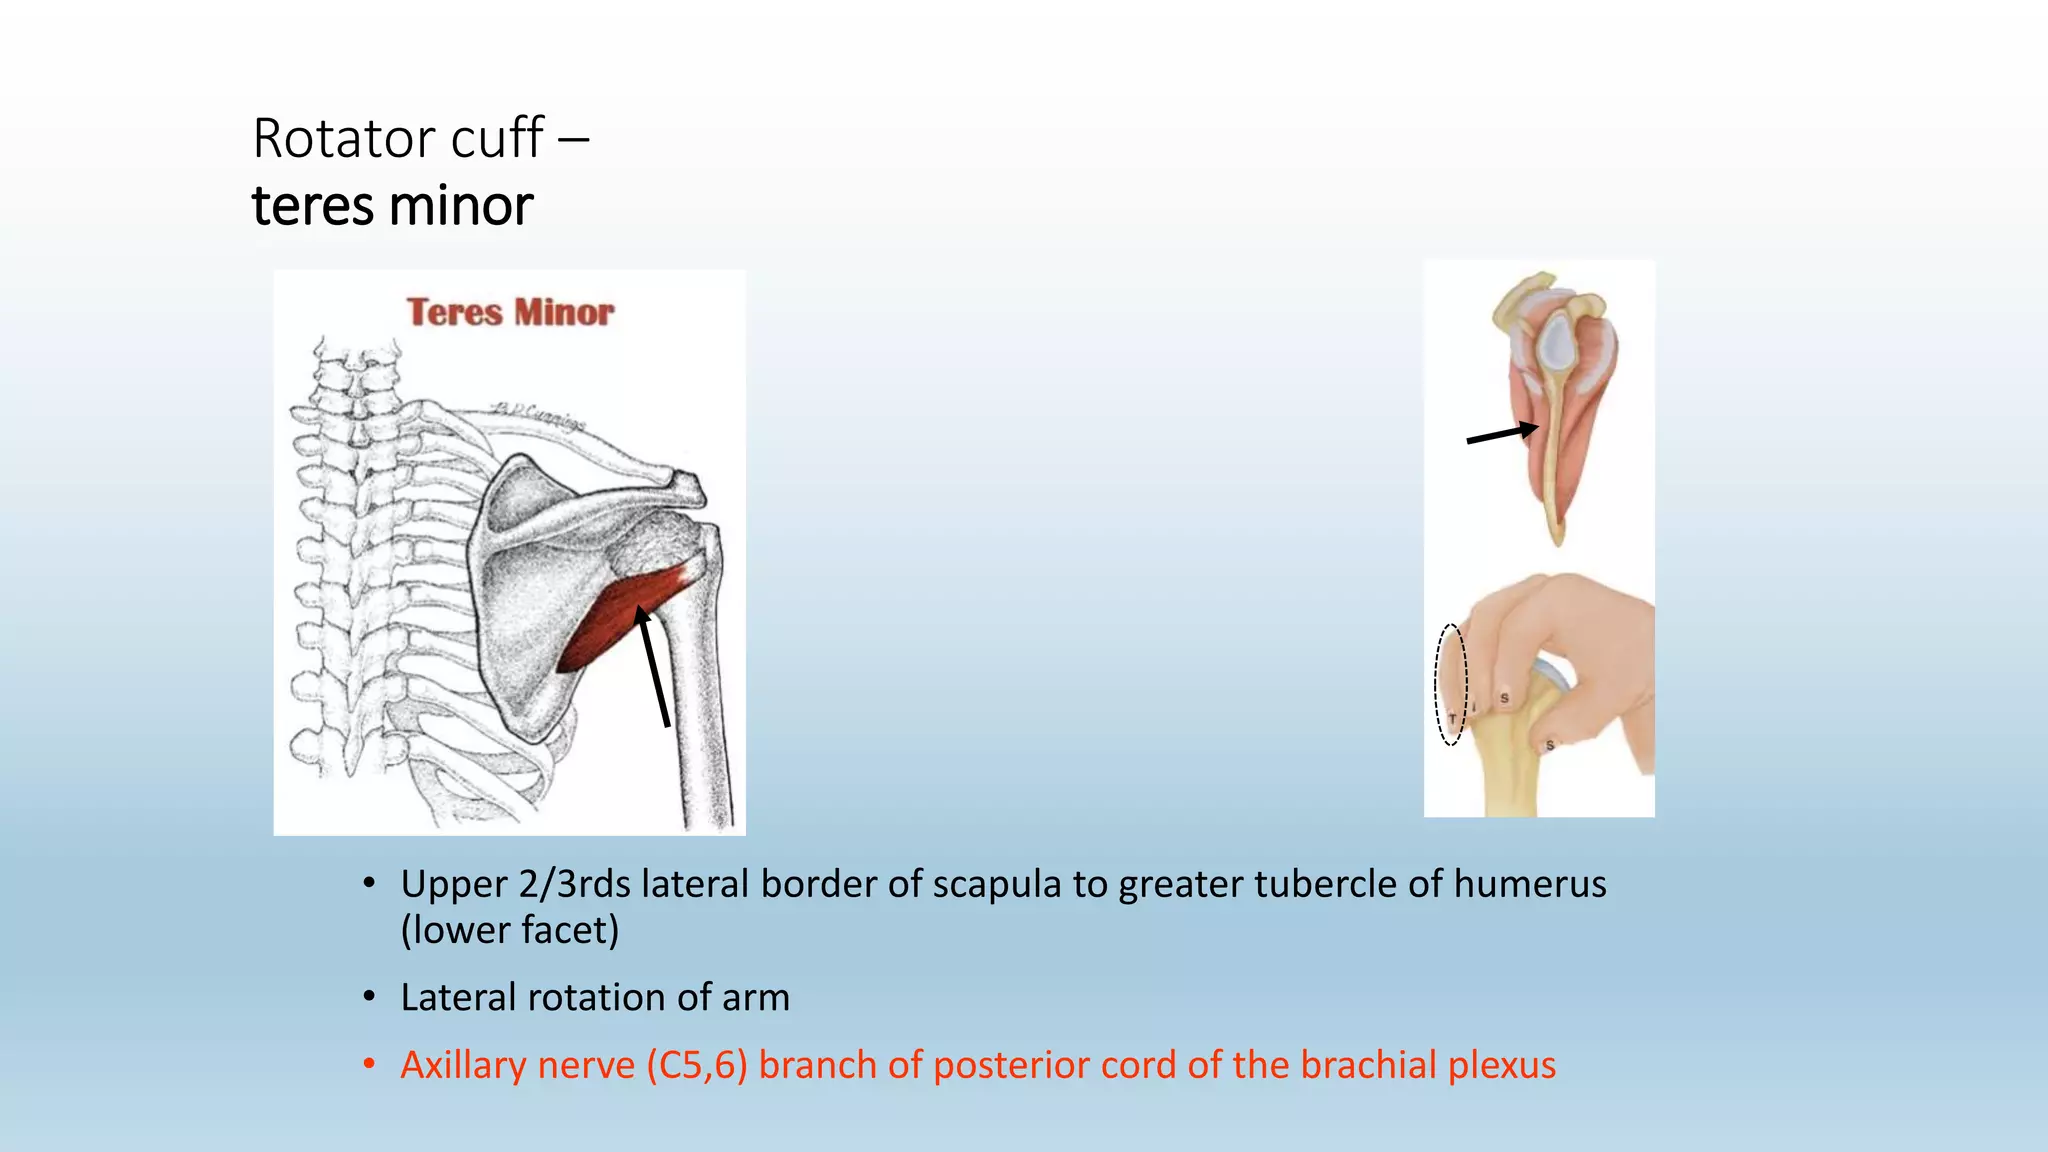

The document summarizes an anatomy revision session on the upper limb. It discusses various muscles of the upper limb including their origins, insertions, innervations and functions. Key muscles covered include the pectoralis major and minor, serratus anterior, deltoid, biceps brachii, brachialis, coracobrachialis, and triceps. It also discusses the rotator cuff muscles and muscles of the forearm including flexor carpi ulnaris and radialis. The session aims to help students identify upper limb muscles and understand their relations to nerves.